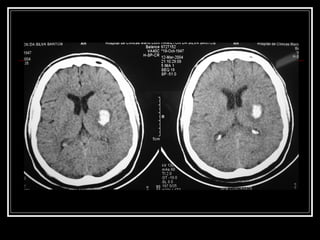

Diagnóstico TC de crânio sem contraste na fase aguda do evento  Limitações: Infratentorial tronco Outros: Lobar? Idade < 45 anos?Hemoventrículo solitário?Sem HAS? RNM e suas variações, arteriografia, etc. para investigação da etiologia do sangramento HDA e HPP (trauma? Anticoagulação? Drogas? Dça hematológica)

Diagnóstico TC decrânio sem contraste na fase aguda do evento Limitações: Infratentorial tronco Outros: Lobar? Idade < 45 anos?Hemoventrículo solitário?Sem HAS? RNM e suas variações, arteriografia, etc. para investigação da etiologia do sangramento HDA e HPP (trauma? Anticoagulação? Drogas? Dça hematológica)